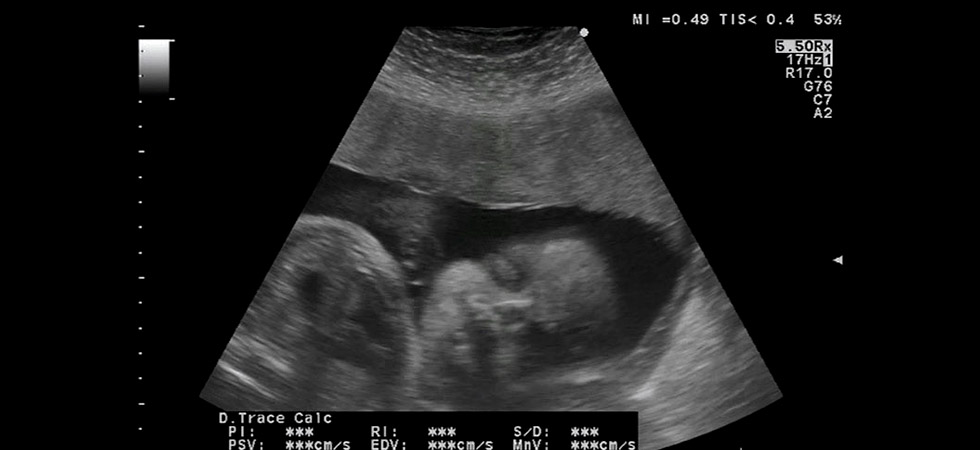

УЗИ

УЗИ на 38 неделе беременности может проводиться разве что по каким-то особым показаниям, ведь, по идее, три плановых ультразвуковых исследования женщиной уже пройдено. Но, если все же требуется уточнить, например, расположение плода в матке, исключить обвитие пуповиной, оценить степень зрелости плаценты, врач может посчитать за необходимое еще одно УЗИ на сроке в 38 недель.

Как и до этого, при проведении УЗИ специалист осмотрит не только малыша, но и состояние матки. Интерес при обследовании представляет размер малыша и соотношение отдельных частей его тела между собой, частота сердцебиения крохи, его положение в матке.

Во время ультразвукового исследования оценит врач также и количество, качество околоплодных вод, исследует структуру и размер, степень зрелости плаценты. Интерес представляет также зрелость шейки матки, ее размеры и состояние в целом.

Фото УЗИ на 38 неделе беременности